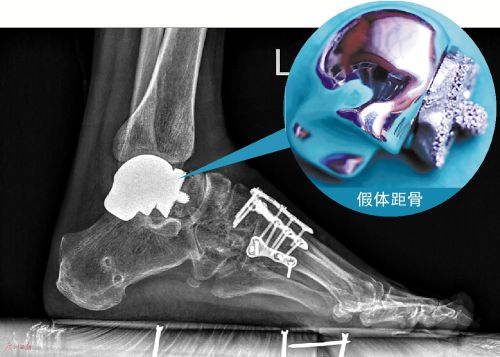

近日,一名在交通事故中左踝关节严重损伤、丢失了半块距骨的女伤者,在南方医科大学第三附属医院顺利接受了国内首例3D打印生物型假体距骨部分置换手术,如今她已经能够下地行走。

原来,今年2月陈女士在汕头陆丰遭遇交通事故,后来她被送到广州的南医三院救治。入院时,她全身多处骨折,踝关节更是开放性损伤严重,内部大半块距骨缺损遗落在现场,无法找回。在处理了全身多处骨折和损伤之后,医生决定等其伤口愈合完好后,再处理踝关节上距骨缺损的问题。7月5日,南医三院足踝外科主任曾参军在陈女士的左足完成了这例3D打印生物型多孔假体距骨部分置换手术,四个多月过去了,陈女士恢复正常行走,关节和原本的功能一样,经过检查,距骨假体已经与自体部分相融合,非常稳定。

根据国内外文献资料报道,距骨部分置换曾有国外专家尝试,但是存在自体距骨跟假体距骨很难实现牢固固定,会发生错位的问题。为了避免这种情况,曾参军主任打算对3D打印距骨假体进行改良,他的团队医生将陈女士的距骨做CT扫描,并三维重建,以右侧踝关节的完整距骨作为镜像模板,打印出患者缺损的距骨假体,且在假体与自体骨的接触面设计多孔结构,内部结构类似蜂窝状,术中将这个钴铬钼合金材料做成的假体植入缺损部位,并将假体接触面凸出的两枚钉棒嵌入自体距骨,两个界面完全贴合。“接驳部位的这些小孔的尺寸都有讲究,大概每一个的直径都要控制在5~6微米,这样才有利于患者自体的骨头生长融合,达到最好的对接。”曾参军告诉记者,这种接驳面的设计也是目前他们还在进行的一项临床研究得出的结论。

术后2个月,患者开始下地行走,踝部力量恢复良好,行走稳定。经过CT复查,医生们发现,陈女士自体距骨已经在往假体的蜂窝孔里生长,这证实了曾主任当初的设想:多孔结构的假体,能促进自体骨长入;距骨部分置换能使自体距骨上附着的韧带及其自体感受器保存完好,这些让假体在体内更稳定,更牢固,使患者的踝关节恢复如初。